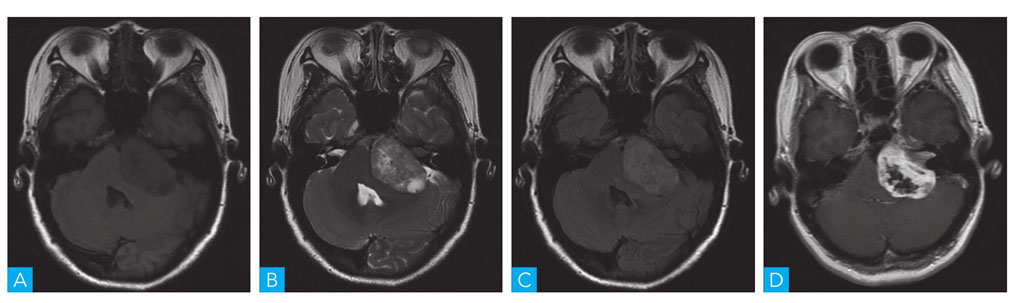

图1-1-3 听神经瘤MRI扫描

A.轴位T1WI;B.轴位 T2WI;C.轴位T2-FLAIR;D.轴位T1WI增强

是桥小脑角区最常见的颅内脑外肿瘤,约占该区占位性病变的85%,肿瘤多单发,多以内听道为中心生长,呈圆形或类圆形,同侧听神经明显增粗,并与肿瘤分界不清,呈“倒逗点”状;肿瘤可囊变,邻近脑实质水肿较轻(图1-1-3)。发生于该区域的弥漫性星形细胞瘤,病灶周围水肿较明显,邻近听神经未见增粗,内听道未见扩大等可与之鉴别。